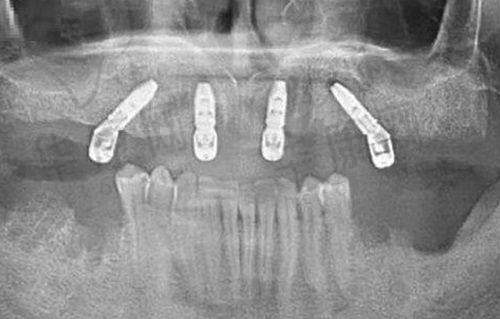

常州京杭口腔在根管治疗方面拥有精良的技术设备。其开展的显微根管治疗,采用蔡司手术显微镜进行操作。在显微镜的精细视野下,医生能够更清晰地观察根管内部的细微结构,大大提高了疏通钙化根管的成功几率,可达91%。这对于一些外院判定需拔除的弯曲根管牙齿,在常州京杭口腔有较大机会成功保留。

同时,医院配备了热牙胶充填系统。热牙胶充填能够使根管充填更加紧密、均匀,有效降低术后根尖病变的复发率。据统计,术后5年根尖病变复发率仅3%,为患者的牙齿健康提供了更可靠的保护。